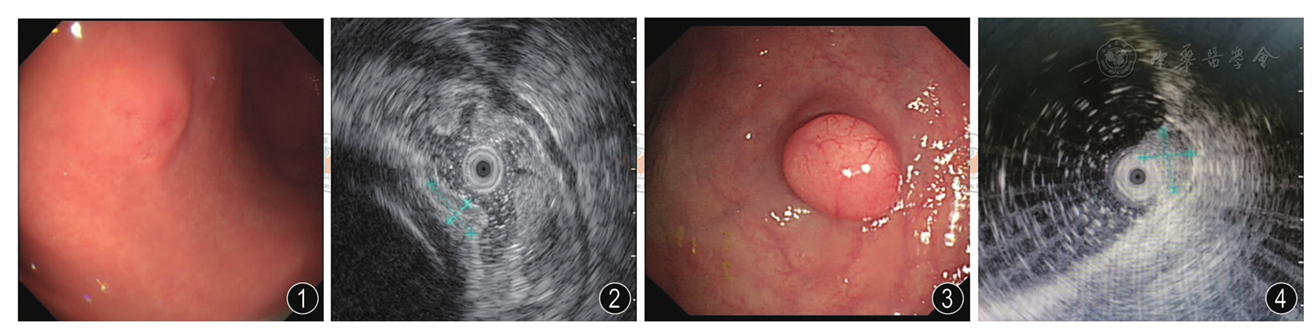

图4 超声内镜检查